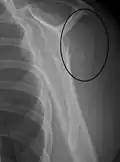

Proximal humerus fracture -